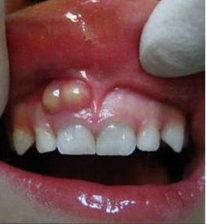

2)根尖囊肿,也称神经根囊肿,由牙齿感染引起;通常见于30-60岁,主要症状是深龋洞,牙齿变色,反复出现牙龈脓包等。

鼻内镜检查单侧中鼻道脓性物(下图)